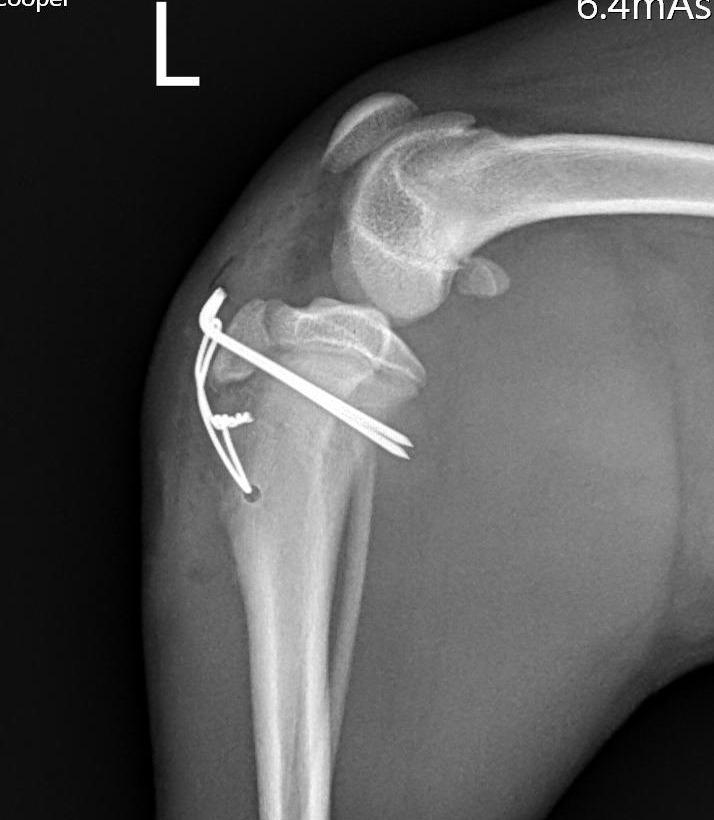

我們練習一下: 第一張照片R是正常的膝蓋, 找找看標記L的第二張 部分哪裡飛起來了呢?

後面兩張就是骨科醫師用骨釘(亮亮一根根) 把骨頭回復到原本該在的位置, 大部分狗狗貓貓都能在3-5天後很好的使用受傷的腳~